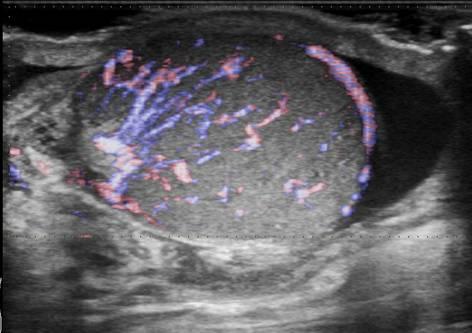

Viêm tinh hoàn - mào tinh

Viêm tinh hoàn – mào tinh

» Thông tin: Nam giới – 34 tuổi.

» Lâm sàng: Sưng đau vùng bìu.

# Tăng kích thước và tín hiệu mạch trên doppler tinh hoàn và mào tinh hoàn.